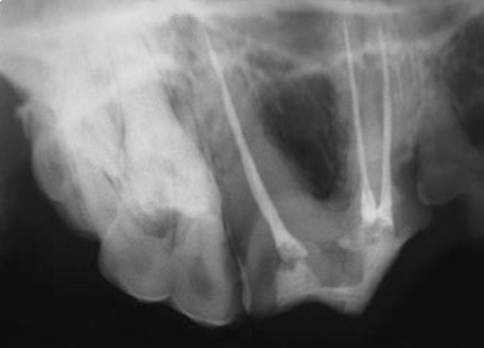

- Осуществляют рентгенологический контроль качества пломбирования.

Методика латеральной конденсации холодной гуттаперчи является простой, относительно дешевой и в то же время очень эффективной. Сущность метода состоит в том, что корневой канал плотно заполняется гуттаперчевыми штифтами в сочетании с твердеющей пастой. При этом достигается очень надежное закрытие апикального отверстия и полноценное заполнение всего просвета корневого канала.Пломбирование корневых каналов начинается с выбора основного гуттаперчевого штифта. Он должен быть того же размера, что и мастер-файл. Отмеряют рабочую длину и делают насечку на штифте – гуттаперчевый штифт не должен доходить до верхушки на 1 мм. Перед тем как ввести основной штифт в канал, подбирают нужный спредер (боковой уплотнитель). Он должен быть того же размера, что и штифт. В высушенный канал с помощью файла вводят силлер. Затем силлер наносят на гуттаперчу и вводят в канал с помощью пинцета на всю рабочую длину. После этого в канал вводят спредер таким образом, чтобы острие инструмента находилось выше апекса на 2 мм, и затем в течение 10 сек. отжимают его в сторону. После выведения спредера из канала в канал вводится дополнительный штифт того же размера или на один размер меньше. Перед введением штифт смазывается эндогерметиком. Затем опять гуттаперча конденсируется спредером. Операция повторяется до достижения полной обтурации канала. Выступающие из канала части гуттаперчи срезаются разогретым инструментом. Излишки эндогерметика удаляются ватным шариком. Затем производят рентгенологический контроль качества пломбирования и накладывают изолирующую повязку (пломба).